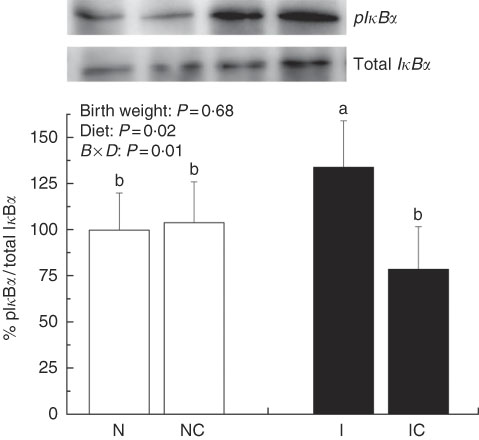

The IUGR rats exhibited higher (P<0·05) phosphorylated IκBα (Fig. 6) and nuclear phosphorylated NF-κB (Fig. 7) levels and lower (P<0·05) cytoplasmic phosphorylated NF-κB (Fig. 8) levels in the liver than in the NBW rats. In addition, the phosphorylated levels of JAK2 (Fig. 9) and STAT3 (Fig. 10) were higher (P=0·24, P=0·01) in the IUGR rats than in the NBW and NC groups. Dietary curcumin supplementation decreased the phosphorylated levels of IκBα (P<0·05) and JAK2 (P>0·05), and NF-κB (P>0·05) in the nucleus and cytoplasm of liver in the IC group.

Fig. 6 Abundance of phosphorylated IκBα in liver of normal birth weight rats (N), normal birth weight (![]() ) rats supplemented with curcumin (NC), intra-uterine growth retardation (IUGR,

) rats supplemented with curcumin (NC), intra-uterine growth retardation (IUGR, ![]() ) rats (I) and IUGR rats supplemented with curcumin (IC) (12 weeks of age). B, birth weight; D, diet; B×D, interaction between the corresponding parameters. Results were corrected for cytoplasmic protein, n 6/group. a,b Mean values with unlike letters were significantly different when a significant interaction was observed (P<0·05).

) rats (I) and IUGR rats supplemented with curcumin (IC) (12 weeks of age). B, birth weight; D, diet; B×D, interaction between the corresponding parameters. Results were corrected for cytoplasmic protein, n 6/group. a,b Mean values with unlike letters were significantly different when a significant interaction was observed (P<0·05).

IUGR neonates are associated with a high risk of inflammation and oxidative stress( Reference Tarryadkins, Fernandeztwinn and Hargreaves 28 ). TNF-α is a key immune modulator, which can activate chemotactic cytokines and produce free radicals, leading to oxidative stress( Reference Starke, Daniel and Dumont 32 ). Furthermore, TNF-α, IL-1β and IL-6 have been implicated as prototype pro-inflammatory cytokines in the pathogenesis of sepsis( Reference Deventer 33 ). Higher TNF-α, IL-1β and IL-6 levels were observed in the serum of IUGR rats, which implied that pro-inflammation occurred in the body. Reports had demonstrated that a strong pro-inflammatory bias existed in IUGR with placental insufficiency( Reference Raghupathy, Al-Azemi and Azizieh 8 ). Significantly high concentrations of TNF-α, IL-1β and IL-6 in IUGR rats were significantly decreased after dietary curcumin supplementation, suggesting that curcumin could reduce inflammatory responses in the serum. These results are similar to those of previous studies in cells( Reference Liu, Shang and Li 34 ) and rats( Reference Soetikno, Sari and Veeraveedu 35 ). The liver is an important organ, and liver dysfunction has been observed in IUGR newborn pigs( Reference Junjun, Lixiang and Defa 7 ). The activities of AST and ALT are positively correlated with portal flow( Reference Kuo, Li and Alfrey 36 ). Hepatic ALT is usually located in the cytoplasm, whereas AST is distributed in the cytoplasm and mitochondrial fractions. However, when the structure of the liver is seriously damaged, ALT and AST are released into the circulatory system, resulting in the improvement of ALT and AST activity in the serum( Reference Nyblom, Berggren and Balldin 37 ). In this study, the activities of serum AST and ALT in the IUGR group were higher than those in the NBW group. The increased activities of serum ALT and AST are generally accepted biomarkers for hepatic dysfunction( Reference Tang, Chao and Xing 38 ). The vacuolisation and cell oedema from the histological examination of liver sections were prevalent in hepatocytes of IUGR rats, which revealed histological damage in the liver of IUGR rats. Meanwhile, fat cells also had mild denaturation. Similar to our findings, IUGR fetuses had a higher activity of glutamate oxaloacetate transaminase and impaired liver function than the normal ones( Reference Liu, Lin and Wang 39 ). After curcumin supplementation, the abnormal levels of serum AST and ALT and liver histological damage improved, and these results were not different from those observed in the normal condition. Previous studies had shown that curcumin could significantly reduce the levels of serum AST and ALT( Reference Zhao, Song and Chai 40 ) and liver injury in mice( Reference Zhang, Xu and Zhang 16 ) and rats( Reference Toydemir, Kanter and Erboga 22 ). Our findings indicated that diets supplemented with curcumin attenuated liver injury and inflammation in IUGR rats. Thus, we concluded that the protective effects of curcumin on the liver may be very important in IUGR rats. To investigate the immunomodulatory mechanisms of curcumin, we detected the expressions of the NF-κB and JAK/STAT pathways in the liver. NF-κB is found in cytoplasm bound to IκB. In response to various stimuli, including cytokines, stress and bacterial pathogens, the latent cytoplasmic NF-κB/IκB complex is activated by phosphorylation( Reference Hiscott, Kwon and Genin 41 ). Phosphorylation of IκB induces their ubiquitination, proteosome degradation and, subsequently, NF-κB release and nucleus translocation( Reference Echeverri, Nancy and Mockus 42 ). NF-κB is one of the most ubiquitous eukaryotic transcription factors that regulate the expression of genes associated with control of inflammatory responses, cellular proliferation/growth, cell adhesion and other processes( Reference Chen, Castranova and Shi 43 ). Our results showed that IUGR induced increased levels of phosphorylated IκBα and nuclear NF-κB and decreased levels of cytoplasmic phosphorylated NF-κB in the liver. Similar to our study, Zhong et al.( Reference Zhong, Li and Huang 44 ) also reported that the IκB was activated and the expression of NF-κB was increased by IUGR. These results suggested that the activation of the NF-κB/IκB complex might be related to increased levels of cytokines in IUGR, including TNF-α and IL-1β. The JAK2/STAT3 pathway is known to be involved in the immune response of numerous cytokines, including IL-6, and activated in response to injury( Reference Yang, He and Hao 45 ). Our results demonstrated that IUGR induced high levels of phosphorylated JAK2 and STAT3 in the liver. The activation of the JAK/STAT3 pathway might be the result of increased IL-6 in IUGR rats. Our results also showed that expression levels of Tnfa, Il1b and Il6 were up-regulated in the liver of IUGR rats. Importantly, dietary curcumin supplementation obviously inhibited the phosphorylation levels of the NF-κB pathway and JAK2 in IUGR rats and down-regulated the expression of those downstream genes. These observations supported that curcumin attenuated inflammation through the NF-κB( Reference Soetikno, Sari and Veeraveedu 35 , Reference Surh, Chun and Cha 46 ) and JAK/STAT pathways( Reference Kim, Park and Joe 47 ) in the liver of IUGR rats, which resulted in the negative regulation of cytokines (TNF-α) and pro-inflammatory interleukins (IL-1β and IL-6)( Reference Reyes-Gordillo, Segovia and Shibayama 48 ).